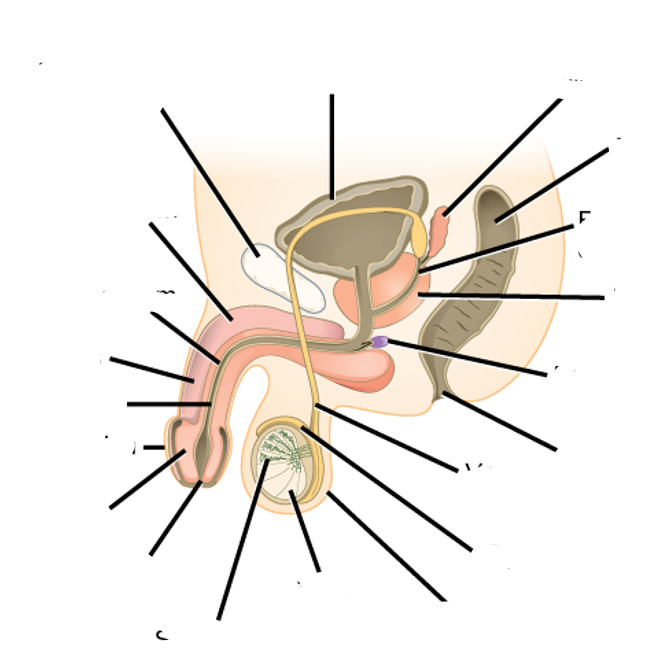

List caudal, cranial, anterior and posterior

list the 2 pieces of anatomy